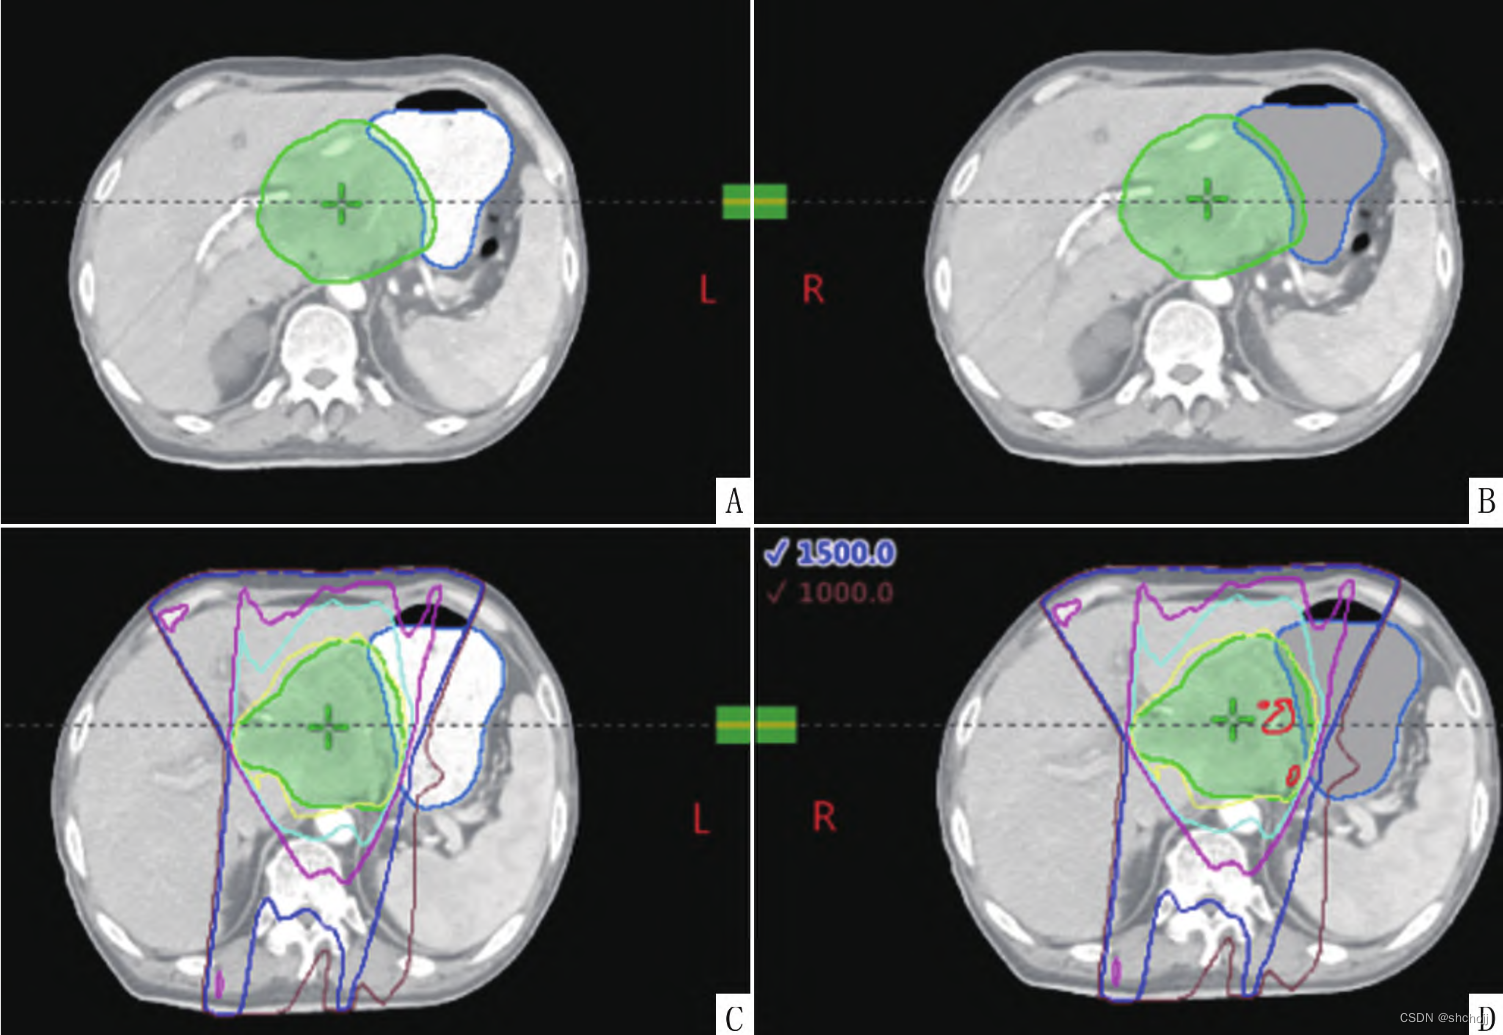

定位包含高密度造影剂图像(A)、水密度替换(B);原计划(C);原计划复制后,相同射野和机器跳数,出现高剂量红色区域(D)